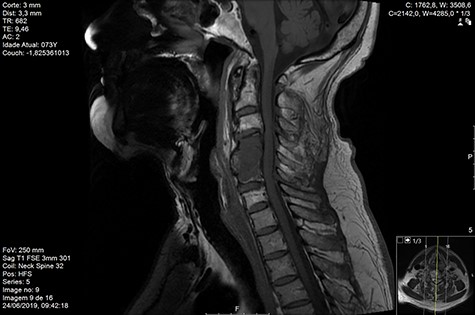

Computed tomography (CT) (Figs 1–3) and magnetic resonance imaging (MRI) (Figs 4–6) of the cervical spine were performed and revealed a lytic lesion involving most of C4, C5 and C6 vertebral bodies with bilateral extension to the posterior spinal elements of C4 and C5 and complete disruption of C4-C5 and C5-C6 intervertebral discs.

The Spinal Instability Neoplastic Score (SINS) [4, 6, 7] for assessing spinal instability from metastatic disease was used and the lesion was deemed unstable (SINS 13), with impending risk of increased neurological damage.

Findings from laboratory tests (serum protein electrophoresis) led to the diagnosis of MM. The patient was placed on a Philadelphia c-spine collar and underwent local 3D external-beam radiotherapy (20Gy in five fractions).